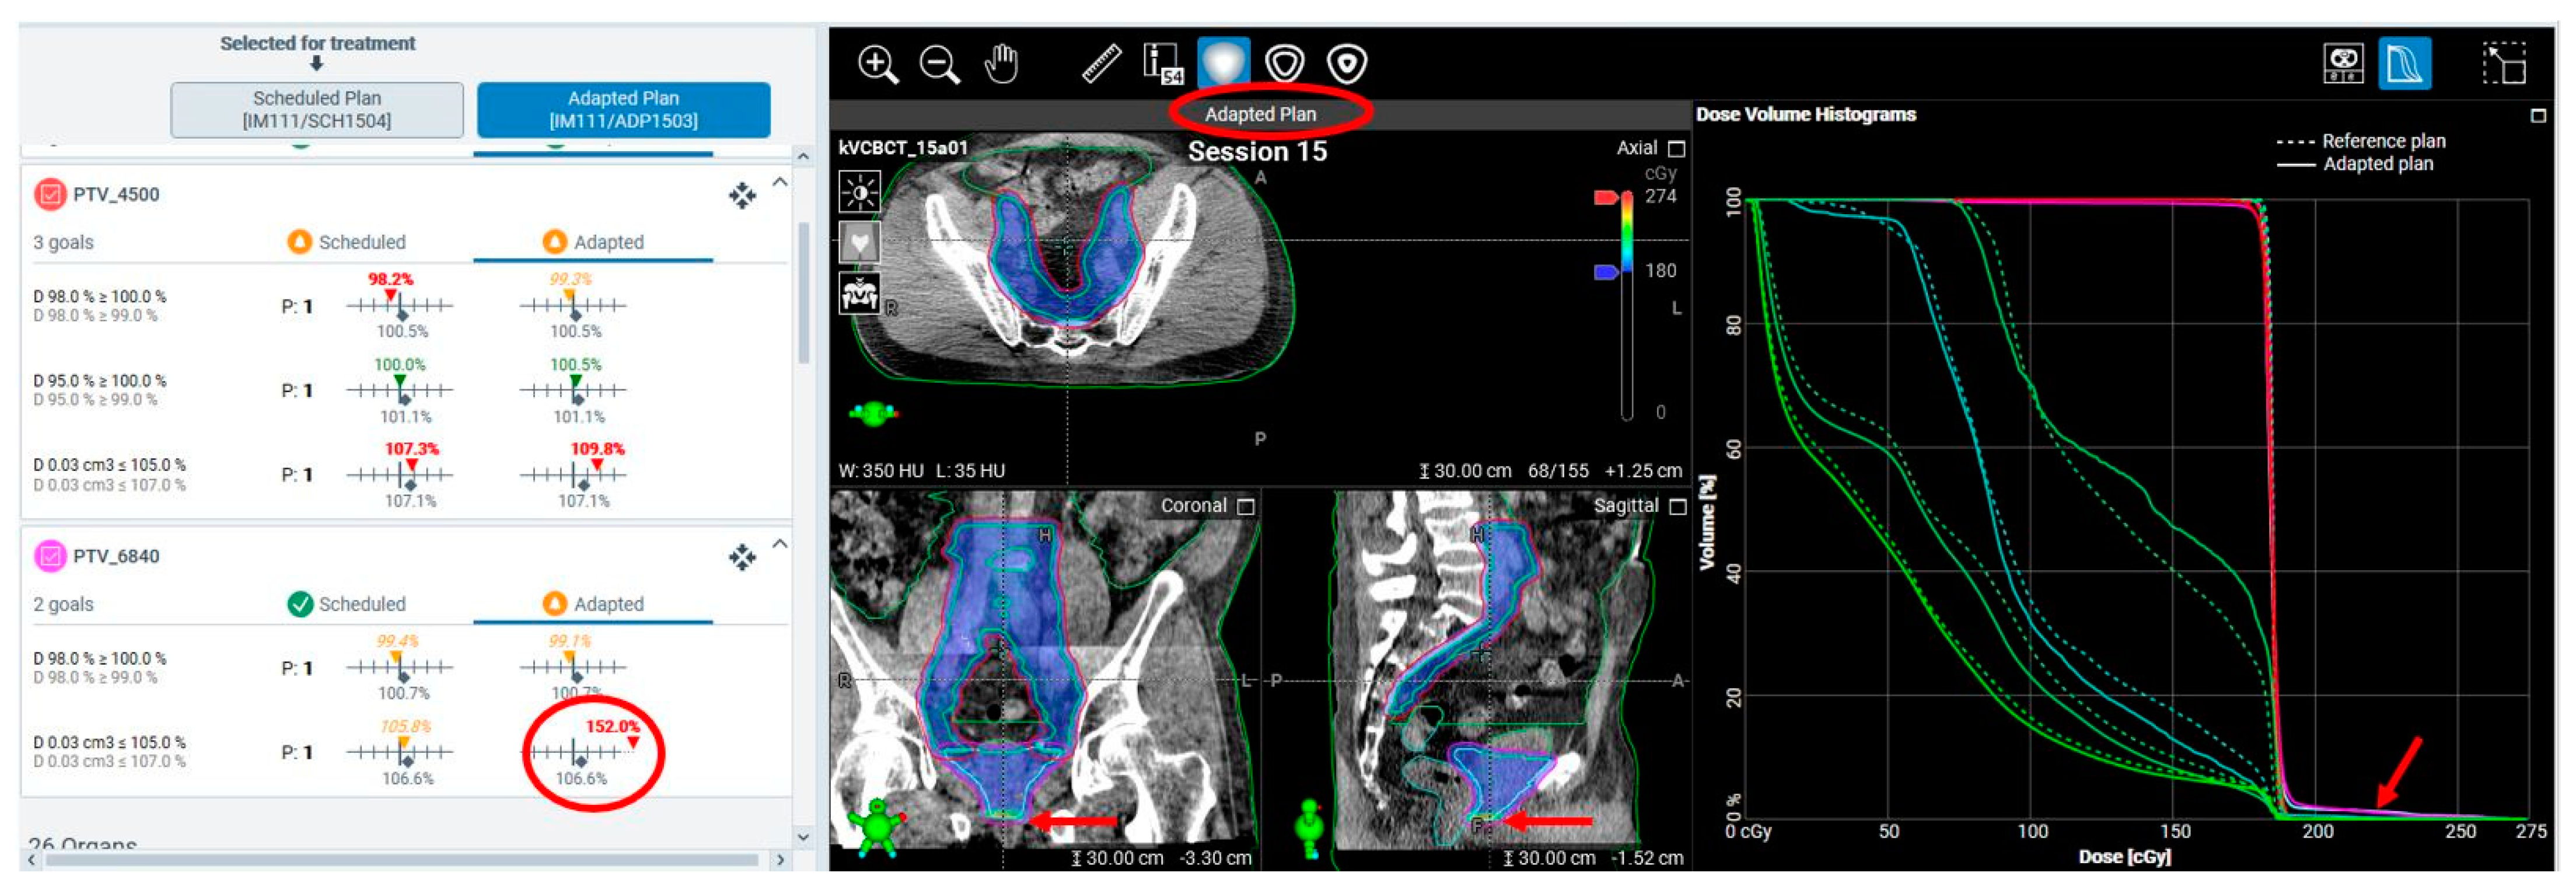

3.2.3. Treatment Planning and Execution Failures